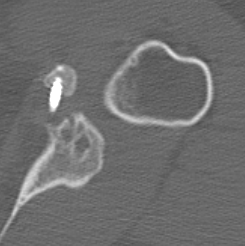

Complete bony union of Latarjet

Nonunion / fibrous union

Osteoarthritis

Nonunion with failure of fixation / recurrent instability

Nonunion with failure of fixation

Latarjet nonunion with hardware failure and displacement of coracoid fragment